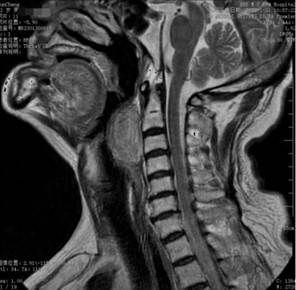

(图1、2核磁检查见口咽至喉咽巨大肿物)

据悉,72岁的孙大爷呼吸困难及吞咽不畅感有近1年的时间,最近两个月加重,严重影响了生活质量。多方诊治无效后,孙大爷来到哈医大四院行相关检查后,发现口咽至喉咽部长了一个巨大的肿物,MRI显示肿物位于咽后间隙内。